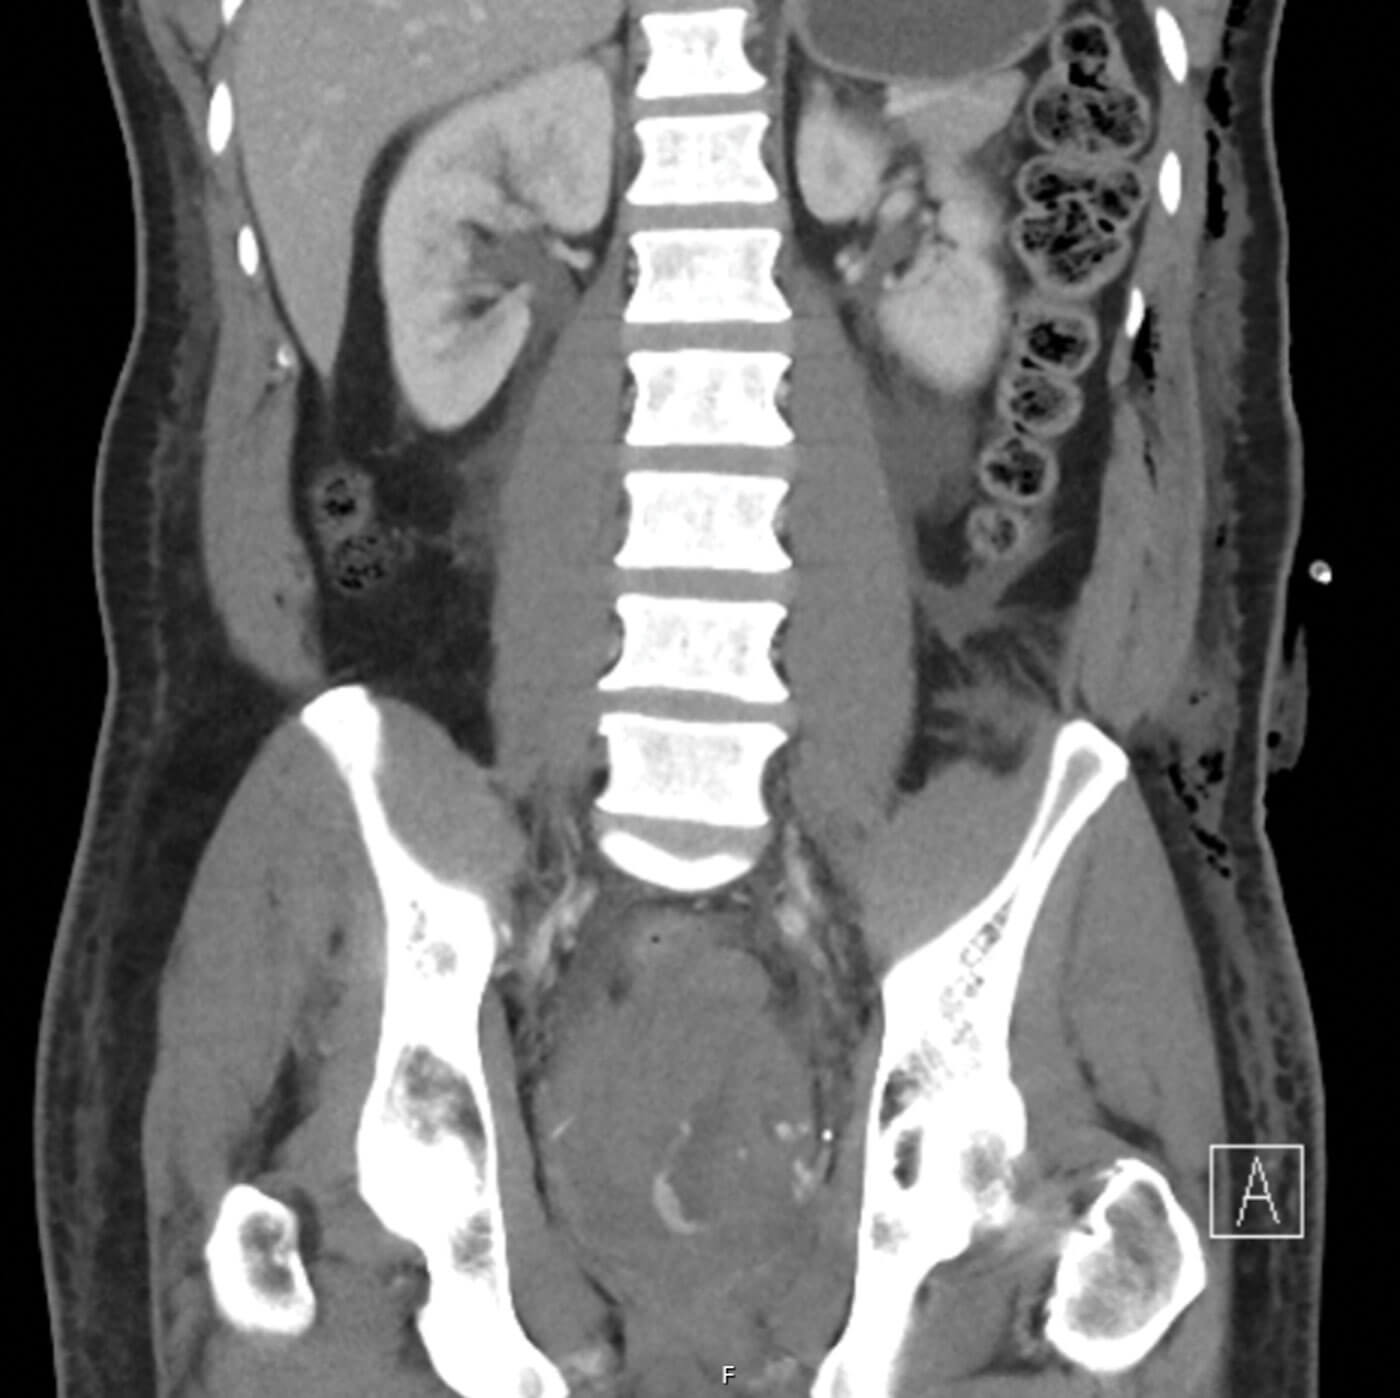

Figure 2: Contrast-enhanced CT pelvis demonstrating a pelvic haematoma

with extravasation of contrast indicating active bleeding.

The patient underwent robot-assisted radical prostatectomy with a request for bilateral nerve sparing. The operation was very challenging due to fibrotic posterior planes and difficulty in nerve sparing and apical dissection with an estimated blood loss of 300mls. His recovery was complicated by a postoperative bleed causing a pelvic haematoma requiring transfusion and super-selective embolisation of the residual left prostatic artery (Grade III complication, Clavien-Dindo classification) as demonstrated in Figures 2 and 3. The patient experienced transient stress urinary incontinence postoperatively and poor erectile function requiring PDE5 inhibitors and vacuum pump device.